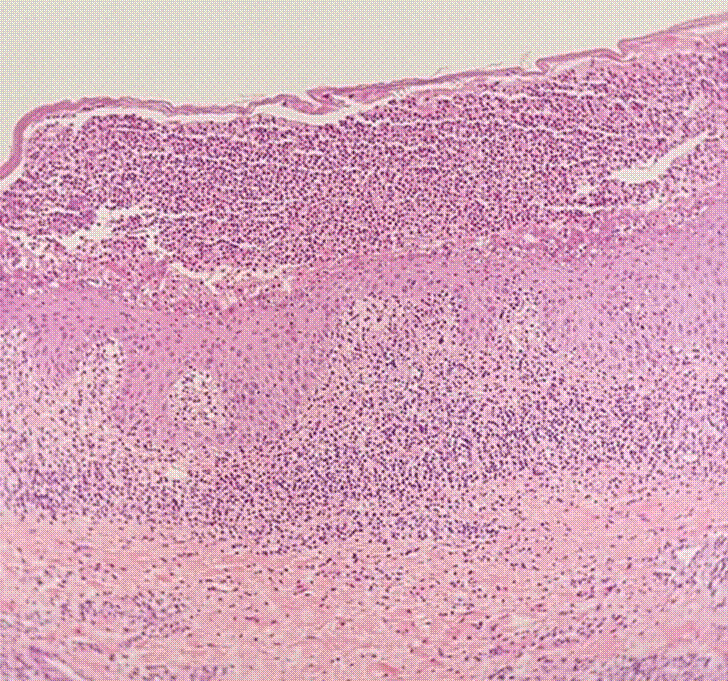

Todos los casos cumplieron los criterios clínicos descritos en la literatura (Tablas 2 y 3) y se analizó la correlación con los hallazgos identificados en la histopatología: acumulación subcorneal de neutrófilos en ausencia de espongiosis y acantólisis (Figura 3). Se realizó inmunofluorescencia directa (IFD) solo en el primer caso, con presencia de anticuerpos IgA e IgG positivos a nivel intercelular, C3 e IgM negativos (Tabla 1).

Los hallazgos histopatológicos fueron compatibles con DPS: pústulas subcórneas con acumulación de neutrófilos, en ausencia de acantólisis o espongiosis. También se observaron infiltrados dérmicos en cinco de las seis biopsias: en el caso cinco el infiltrado fue de predominio eosinofílico, en el caso seis fue de tipo linfocitario y en los demás fue de predominio neutrofílico.